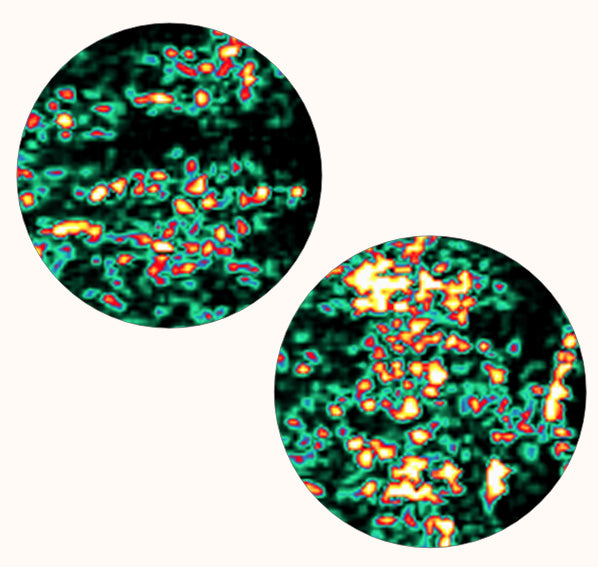

Results may vary, but generally, you will start noticing results within 4 weeks, and for complete results, continue taking it regularly for 60 days.

Yes, the source of collagen is important due to varying levels of absorption and effectiveness. The fish collagen used in Youth Booster is known for its high absorption rate and ability to transfer into deeper layers of the skin.